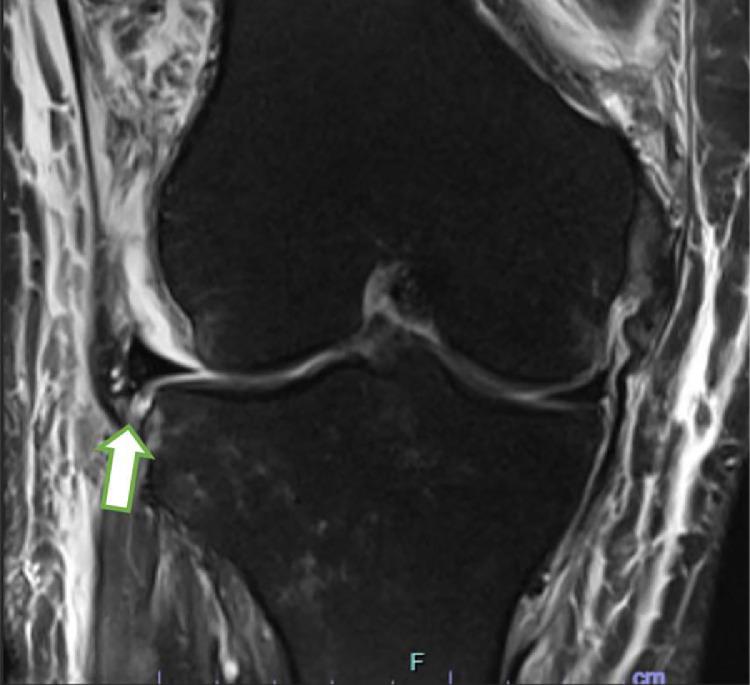

Traumatic dislocations of the knee can result in significant soft tissue damage including multiligamentous and meniscal knee injury. When a meniscal tear involves the posterior horn, the meniscus loses one of its attachments to the tibia and can become extruded from the joint. Stener-like lesions of the knee have been reported throughout the literature; however, they have been exclusively described as a distal tear of the medial collateral ligament (MCL) lying superficial to the pes anserine tendon which prevents anatomic healing. The purpose of this report is to present a previously unreported unique variant of a lateral meniscus tear in the setting of a MLKI. In this case presentation, the lateral meniscus became extruded superficial to the intact lateral collateral ligament (LCL) resulting in a Stener-like lesion. Corrective recognition of lesions like these and timely surgical intervention is recommended to restore native anatomy and prevent chronic pain, instability, and premature degenerative disease. Level IV, Case report.

膝关节创伤性脱位可导致严重的软组织损伤,包括膝关节多韧带和半月板损伤。当半月板撕裂累及后角时,半月板失去其与胫骨的一个附着点,可能会从关节中挤出。膝关节类似斯滕纳(Stener)病变在文献中已有报道;然而,它们仅被描述为位于鹅足肌腱浅面的内侧副韧带(MCL)远端撕裂,这会妨碍解剖学愈合。本报告的目的是介绍一种在多韧带膝关节损伤(MLKI)情况下外侧半月板撕裂的先前未报道的独特变异。在本病例报告中,外侧半月板在完整的外侧副韧带(LCL)浅面挤出,导致类似斯滕纳病变。建议正确识别此类病变并及时进行手术干预,以恢复正常解剖结构,预防慢性疼痛、不稳定和过早的退行性疾病。四级,病例报告。